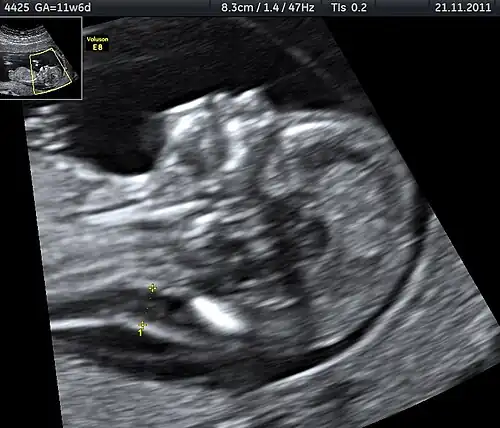

Tetrasomy 9p

Tetrasomy 9p is a rare condition in which people have a small extra chromosome that contains two copies of part of chromosome 9, in addition to having two normal chromosome 9's as well. This condition may be diagnosed by analyzing a person's blood sample since 9p is found in high concentrations in the blood. Ultrasound is another tool that may be utilized to identify tetrasomy 9p in infants prior to birth. Prenatal ultrasound may reveal several common characteristics including: growth restriction, ventriculomegaly, cleft lip or palate, and renal anomalies.[30]